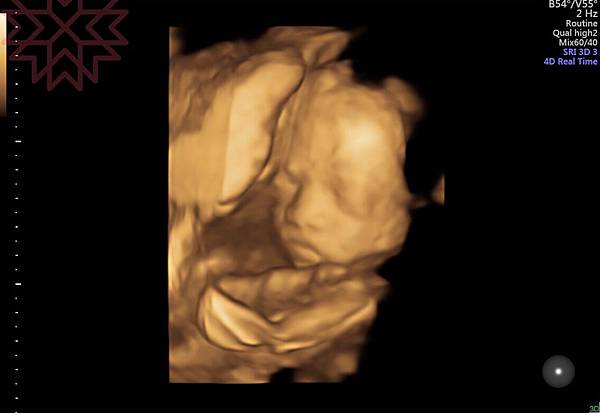

今天進行了第三次的產檢,雖然已經看了很多次螢幕上『外星人』樣的寶寶,但每次照超音波時都還是無比的期待。今天的寶寶依舊活潑,難怪我常常可以感覺到他動來動去,很像不用睡覺ㄧ樣;寶寶有乖乖的長大,但體重好像比平均值來的低,頭圍也比平均值小了些,但都在正常的範圍,照3D圖時也可以清楚的看見五官囉,好像有點像我。至於上次產檢發現的前置胎盤還是沒有移動位置,而且好像是所謂的完全性前置胎盤,目前能做的就是每次產檢的追蹤,若有任何出血的症狀,要馬上就醫;我有在網路上看到一些注意事項,然後就是希望30週後胎盤能夠慢慢的回到正常的位置。

附上我們家的小帥哥特寫